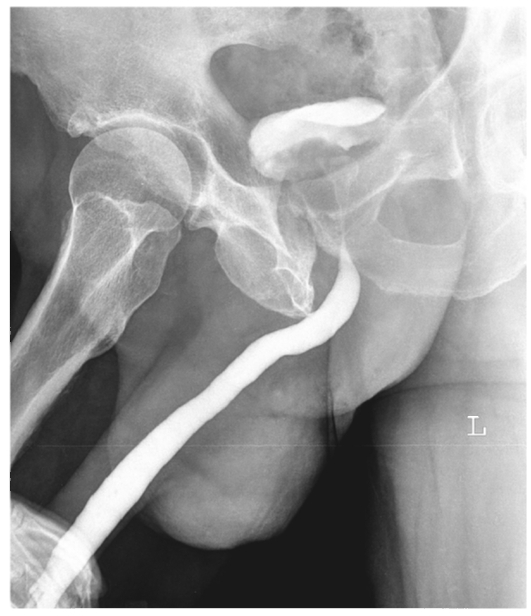

Основными методами верификации стриктуры уретры является

Основными методами верификации стриктуры уретры является 111 фотографий